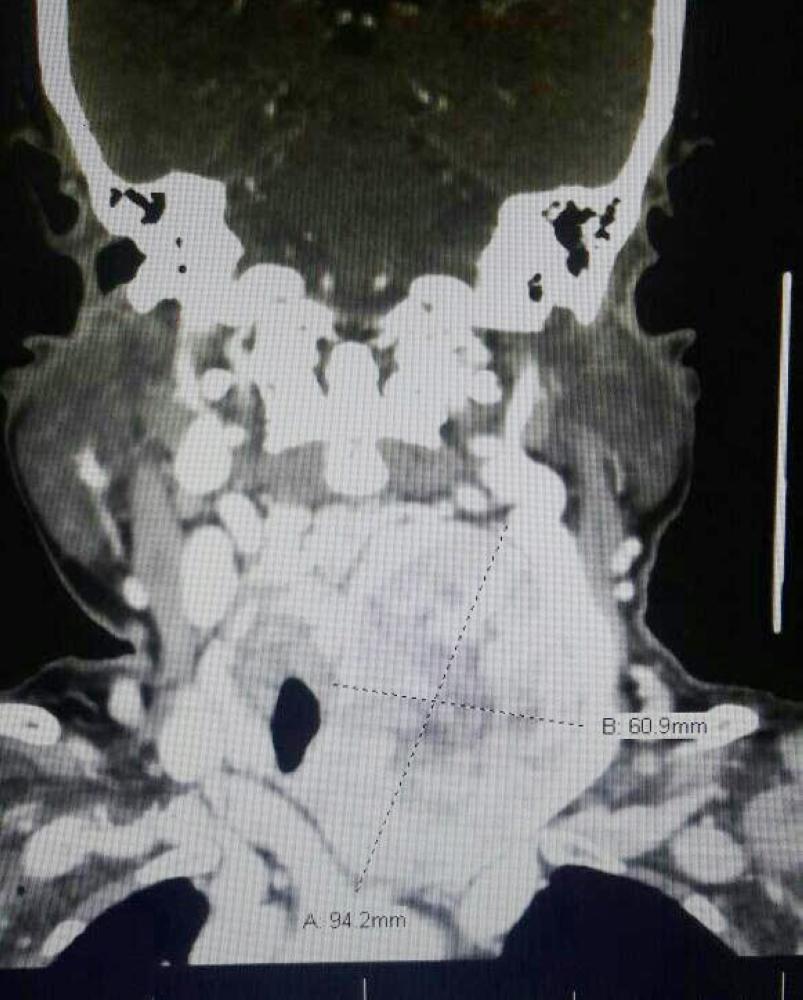

أنهى فريق طبي من قسم الجراحة العامة بمستشفى الملك خالد بنجران، معاناة مريضة (82 عاما)، بتدخل جراحي باستئصال ورم كبير غير حميد في الرقبة ممتد إلى تجويف الصدر أزاح القصبة الهوائية إلى الجهة اليمنى، ما أدى إلى صعوبة التنفس والشعور بالاختناق مع تغير في الصوت وصعوبة في البلع.

ورم المسنة في صورة الأشعة. (عكاظ)